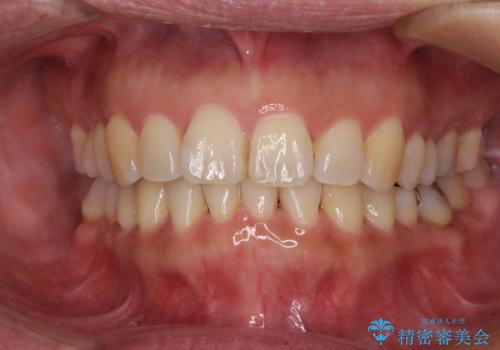

- 上下前歯の叢生を気にして来院された患者様です。

費用を抑え、期間もあまりかけずに治療をしたいとのことで、インビザライン・ライトを用いて矯正治療を行うこととしました。

インビザライン・ライトは、製作できるアライナーの枚数に制限があるため、移動可能な量に限りがあります。

一方で、半年から1年程度で治療を終えることができるため、軽度の歯列不正の患者様には大変お勧めです。